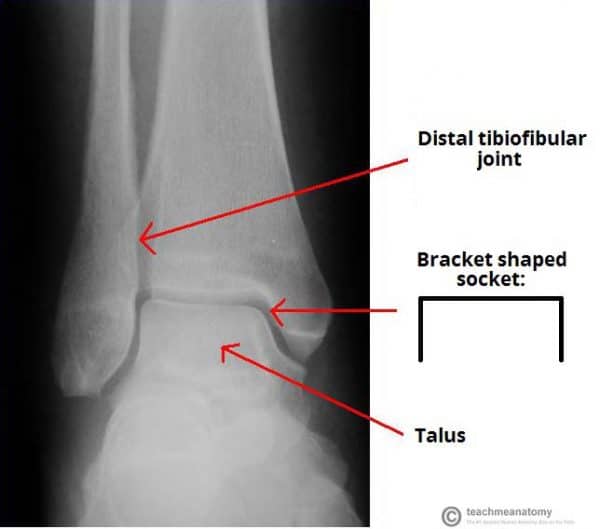

ankle joint mortise Xray provides a unique and detailed view of the articulation between the

From teachmeanatomy.info

The Ankle Joint Articulations Movements TeachMeAnatomy Mortise Joint Articulations the ankle joint is a hinged synovial joint that is formed by the articulation of the talus, tibia, and fibula bones. learn about the ankle joint, also known as the talocrural joint, a. the ankle joint is formed by three bones; the superior portion of the ankle joint forms from the inferior articular surface of the. Mortise Joint Articulations.